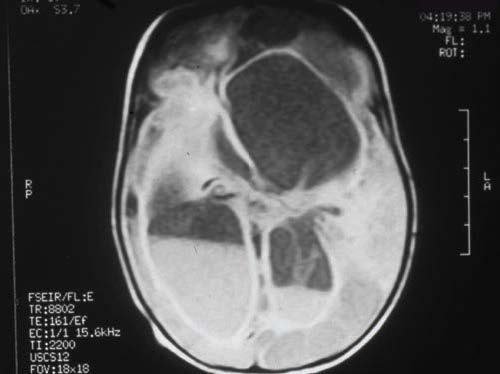

Neha Gupta, MD; Magda Mendez, MD, FAAP; Saurabh Talathi, MD, MPH; Sergey Prokhorov, MD; Maritza Feliz, MD; Naresh Reddivalla, MD

An 8-year-old boy was admitted for evaluation of severe intermittent headache, ataxia, confusion, and slurring of speech.